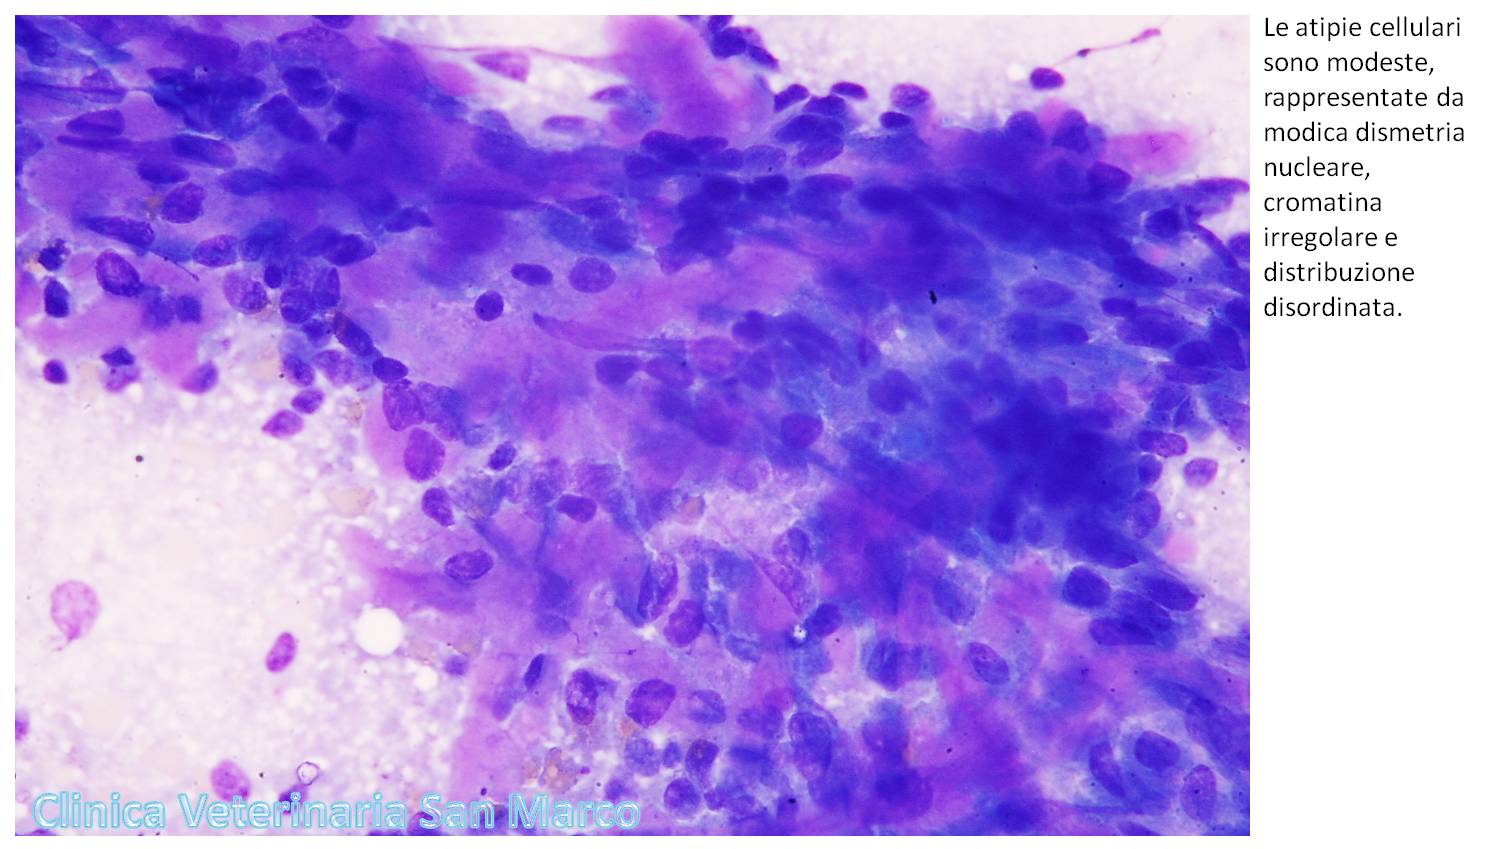

per l’esfoliazione di elementi epiteliali a scarso citoplasma cuboidale

indistinto, basofilo, contenente nucleo rotondo, modicamente dismetrico, a

cromatina irregolare, organizzati in lembi discoesi, nel cui contesto manifestano

frequente disposizione in figure acinari oppure si organizzano circondando la

deposizione di materiale denso eosinofilo in zolle od in strutture filamentose.

Il quadro citologico esprime una neoplasia epiteliale

maligna con aspetti secretori. Considererei la possibilità relativa ad un

adenocarcinoma polmonare, oppure l'estensione metastatica di altre neoplasie

epiteliali ghiandolari metastatiche, tra le quali ipotizzerei soprattutto una

primitività mammaria; consigliata stadiazione clinica accurata, a cui assocerei

un esame citologico dei noduli mammari allo scopo di stabilire un parallelo

eventuale con i rilievi osservati nel polmone.